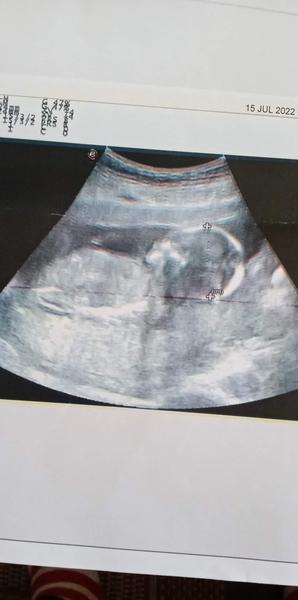

Mám 42rokov.Som v 18tt ,zajtra začínam už 19sty ,bábo má 12,4cm ,včera som bola u lekára robil mi sono povedal len toľko že výsledky vyzerajú byť ok,no nevyznám sa moc do toho čo je na papieri ,keď sa niekto vyzná či tie čísla Papp a hcg sú dobré?

@marcela19791979 babo malo 17.5. 12,7 mm. Teda este v máji nie teraz

@marcela19791979 babo sa v 18tt uz neda zmerat na dlzku... crl sa meria do 13+6 potom je babao akoby skrutene do Cecka. Preto sa prve sono kde sa hodnoti ako taky vek babatka robi od 11+0 do 13+6 a nasledne potom sa crl nemeria!! Dalsje sono tzv morfologicke sa rpbi od 20tt do 22tt a posledne 3. Od 30 do 32tt kde sa hodnotia prietoky. Neviem kto tj povedal ze babo ma 12.4cm ale pochybujem ze je to presny udaj. Klud..objednaj sa na morfo sono